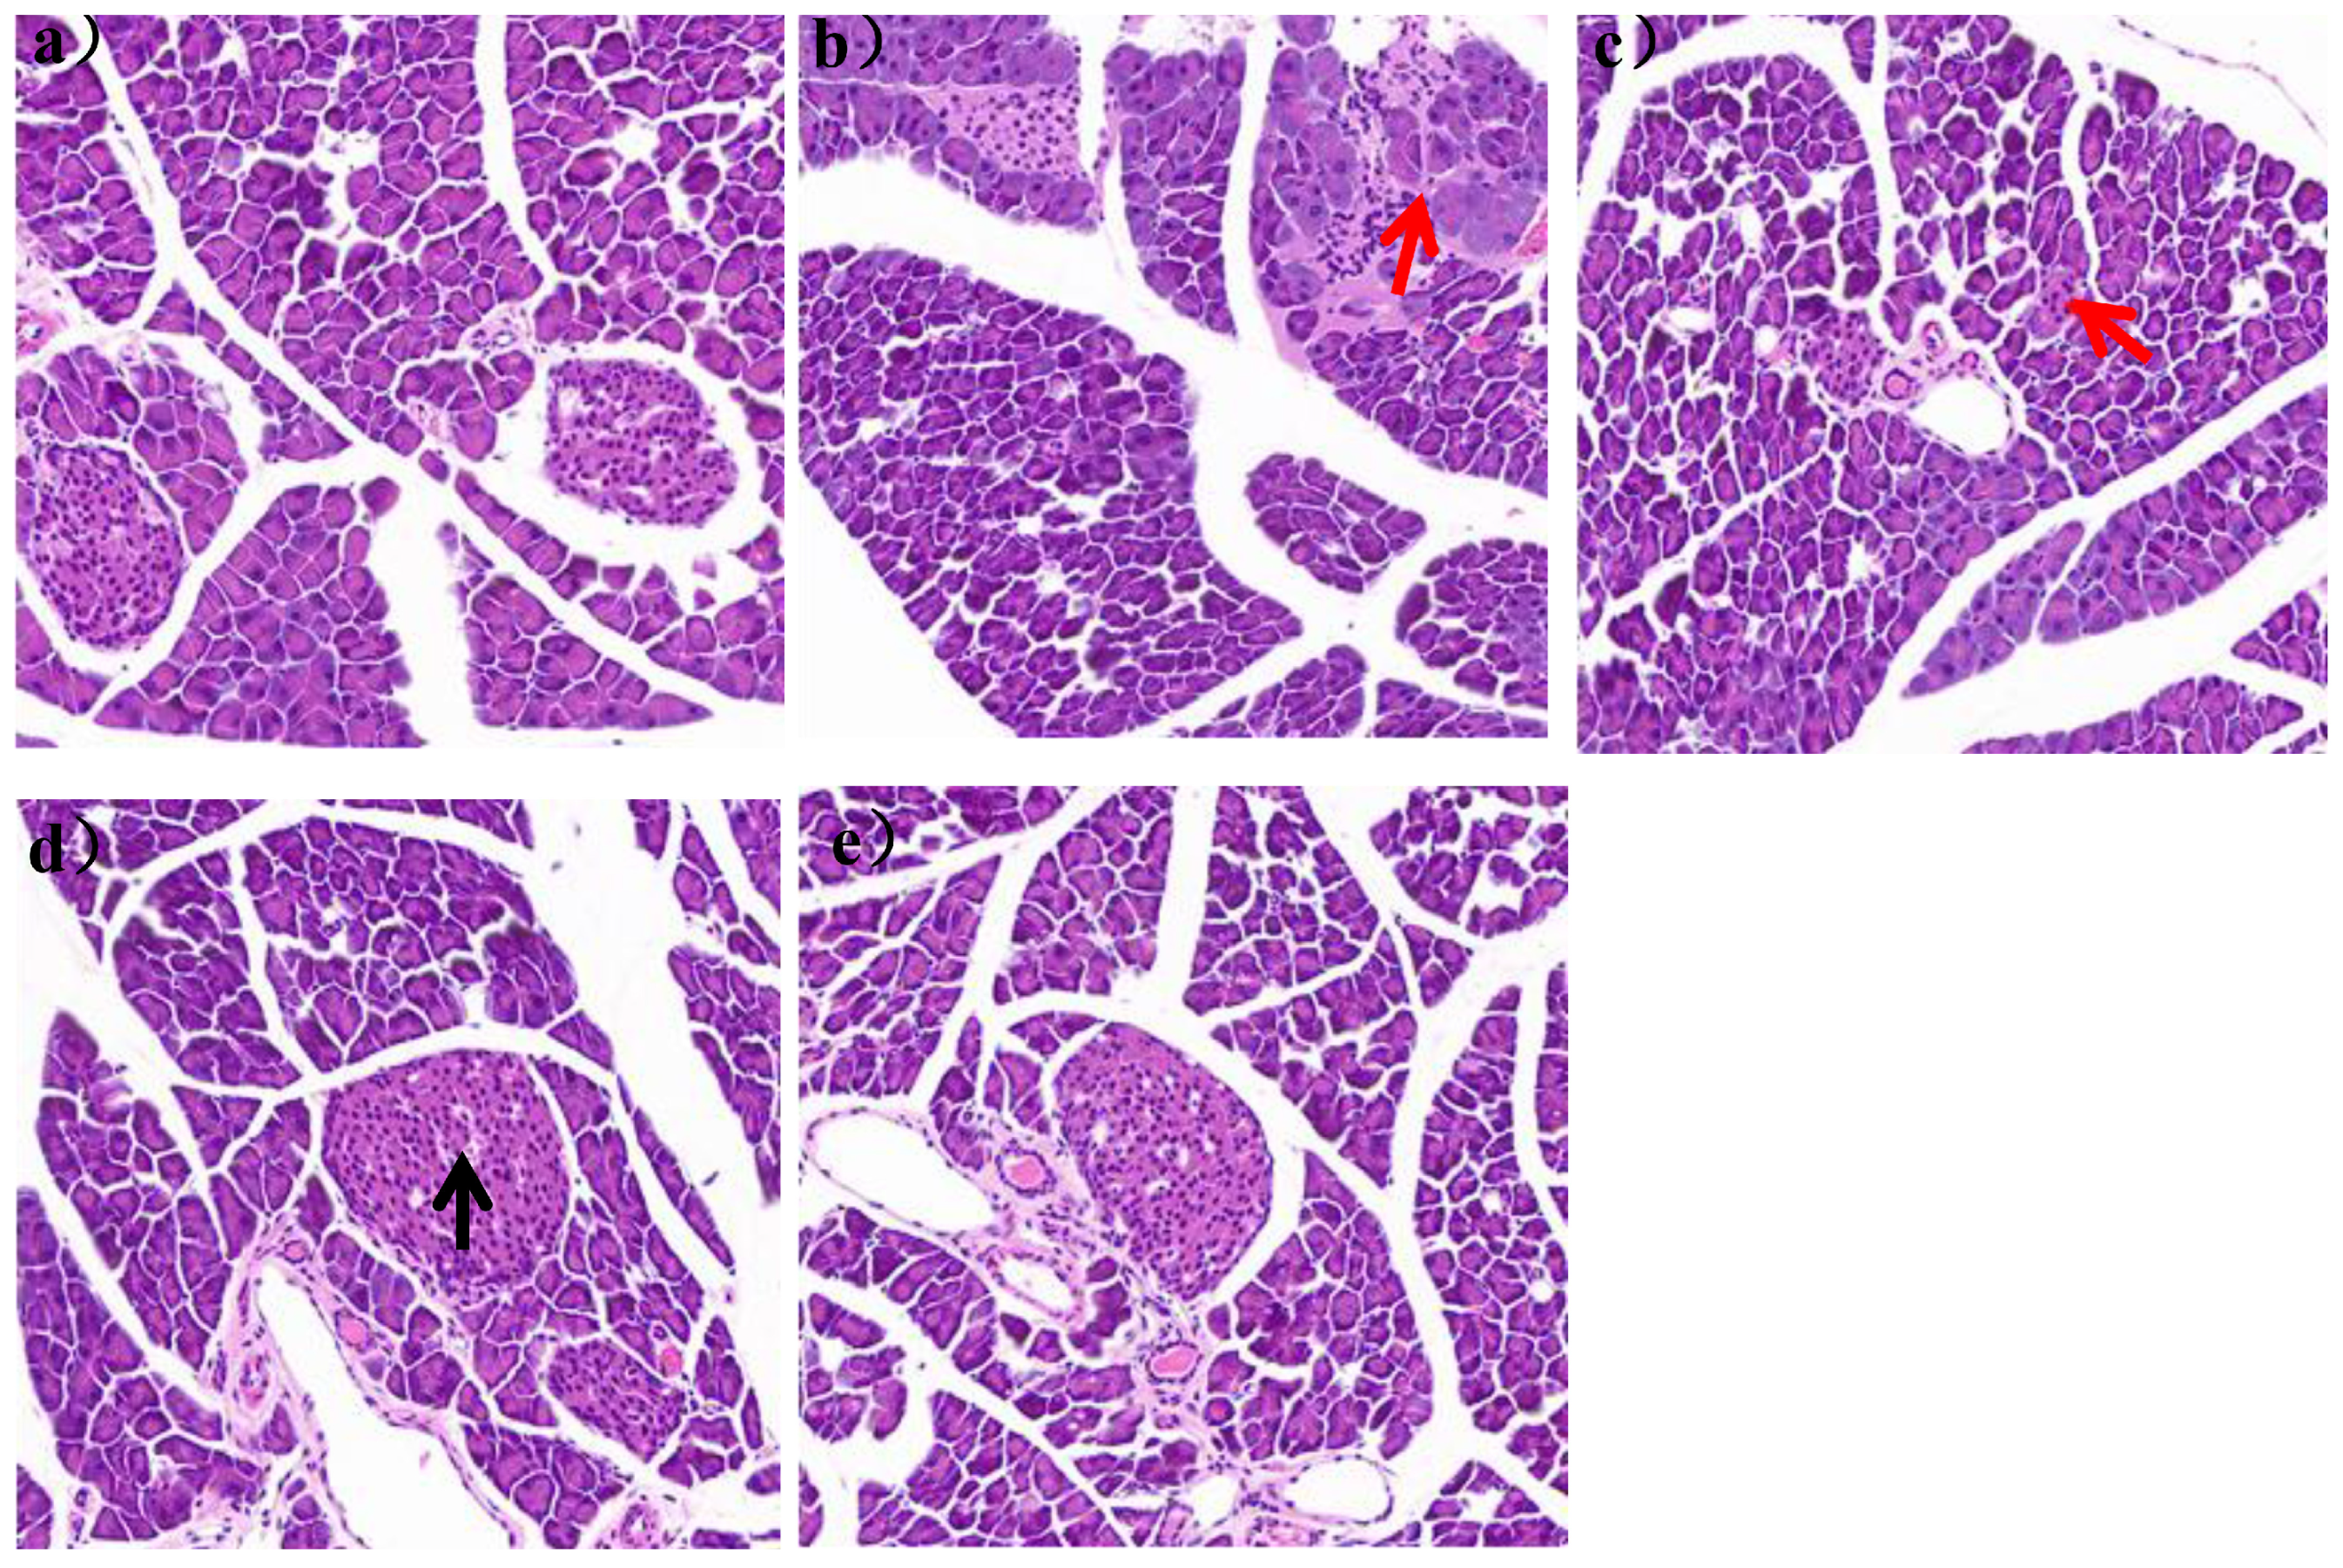

It could be seen in Figure 6a that the pancreatic tissue structure of mice in group N was clear, without vacuolation and inflammatory cell infiltration.

The islet was a spherical cell-like structure, distributed between the acinus, with a clear boundary with the surrounding glands. And the islet cells were arranged regularly, with high cell density and abundant cytoplasm. In the HFD group, the islets were distributed between the acinus and the surrounding glands, and the islets were not clearly demarcated with the surrounding glands. The number of islets was also significantly reduced, with a large number of inflammatory cells infiltrating, as shown by the red arrow in Figure 6b. After 7 weeks of L. paracasei JY062 intervention, compared with the HFD group, the arrangement of islet cells gradually became regular, the number of islets gradually increased, and the boundary between islets and surrounding glands gradually became clear. In the LPH group, some telangiectations occurred, as shown by the black arrow in Figure 6d.

Figure 6. Image of pancreatic section (scale bar = 50 μm). (a) mice pancreas of N group; (b) mice pancreas of HFD group; (c) mice pancreas of LPL group; (d) mice pancreas of LPM group; (e) mice pancreas of LPH group; The black arrows represent telangiectasia; The red arrows represent inflammatory cells.